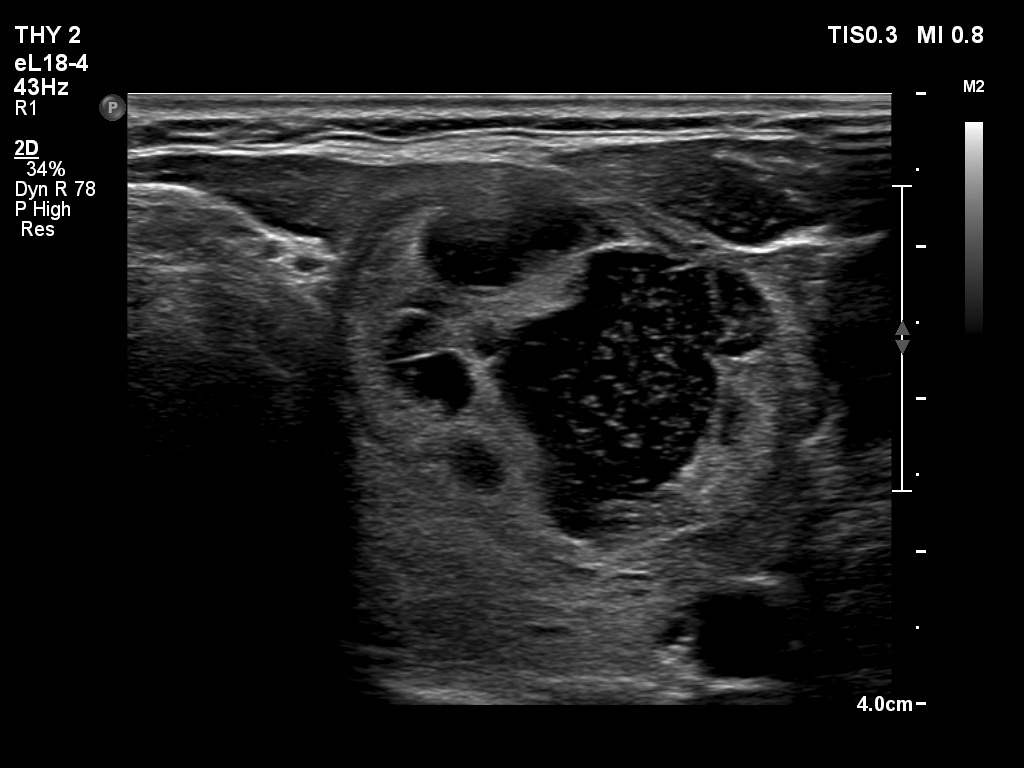

Ultrasonography. The thyroid was echonormal. The right lobe contained several discrete areas without any clinical significance. There was multi-chambered cystic nodule in the left lobe. The nodule had echonormal solid part and presented halo sign.

- The distinction between a multi-chambered cyst and a spongiform cyst is important, because in the latter the risk of malignancy is practically zero. In spongiform cysts almost the entire nodule is composed of cystic areas, and there is very small proportion of solid areas.

- The cyst has just started refilling after the evacuation.